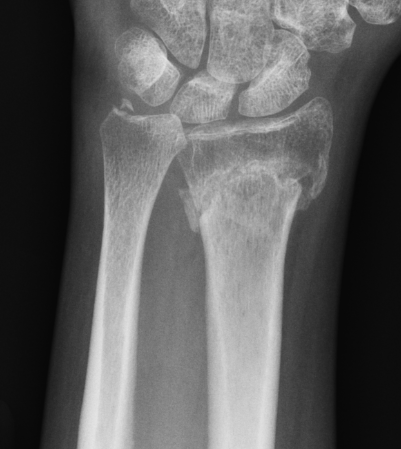

DRUJ instability after distal radius fracture

Two settings

1. Ulna styloid fracture

2. No ulna styloid fracture / TFCC injury

Ulna styloid fractures

Ulna styloid fractures occur in half of all distal radius fractures

Anatomy

Ulna styloid

- bony projection from ulna

- fovea at base for soft tissue attachments

- TFCC / radio-ulna ligaments